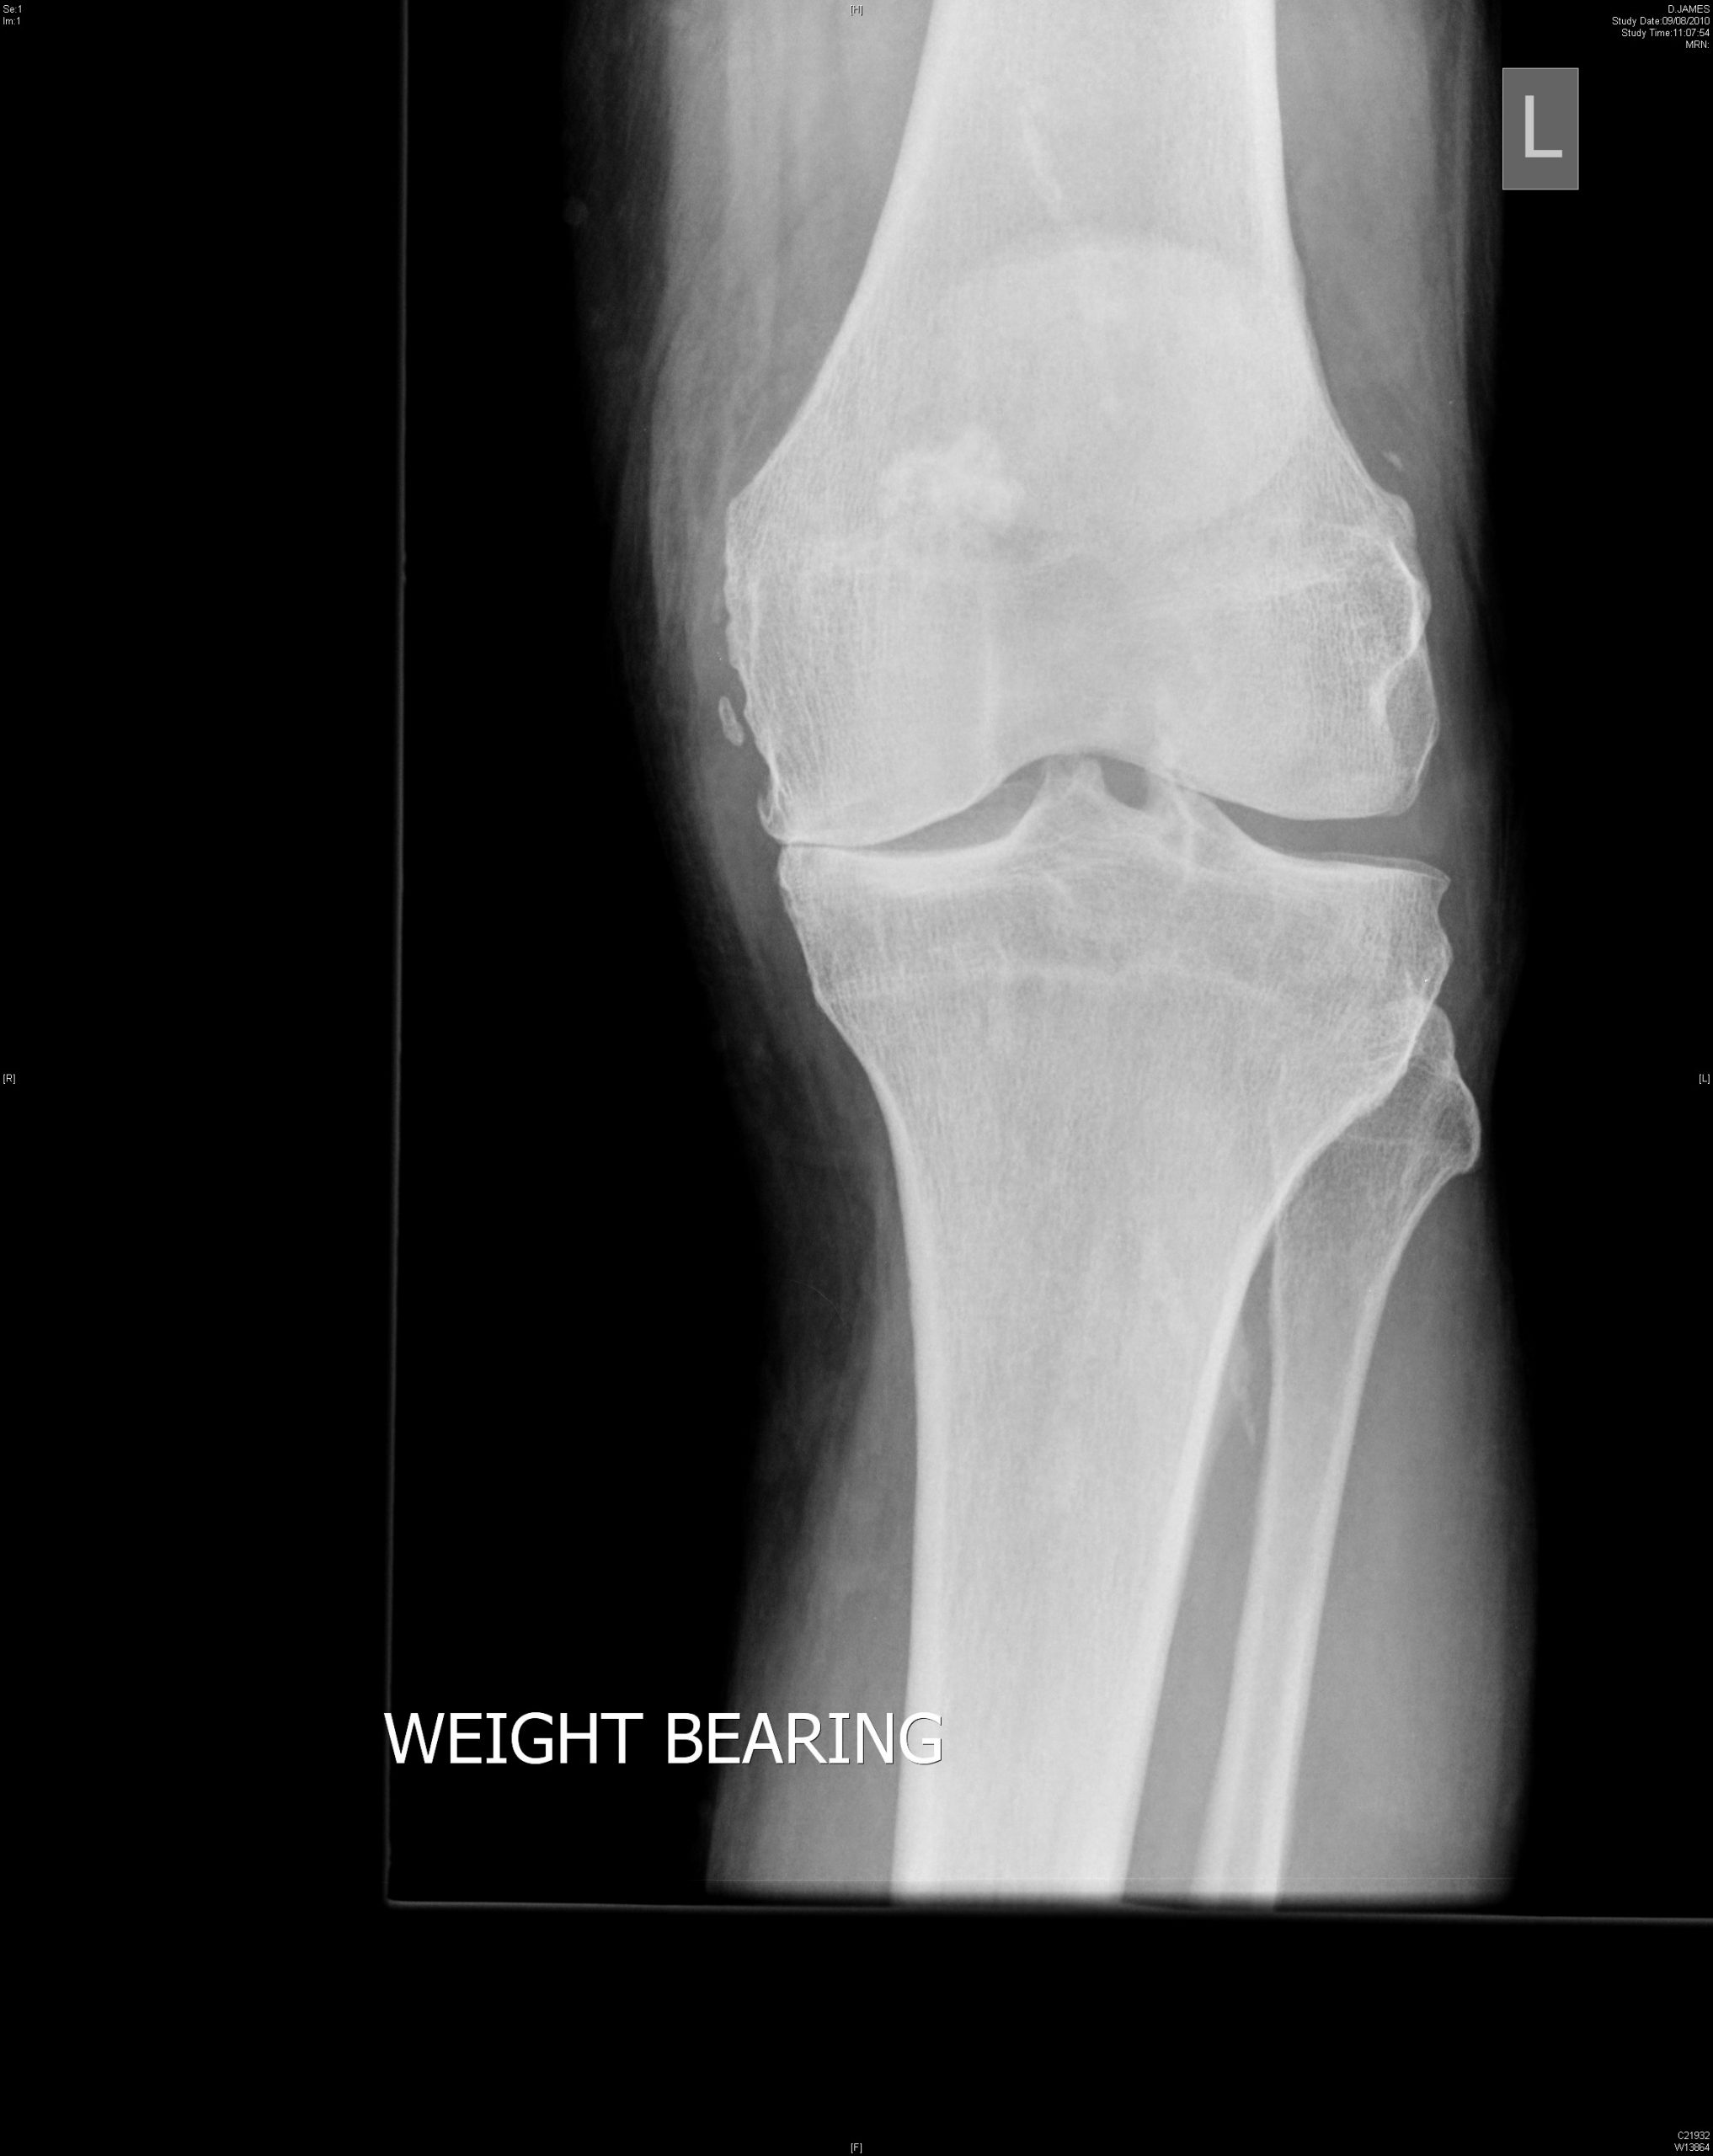

Our services are lead by Simon Palmer who is a Consultant Orthopaedic Surgeon with specialist training and experience in all aspects of knee surgery, including minimally invasive surgery and partial knee replacement.